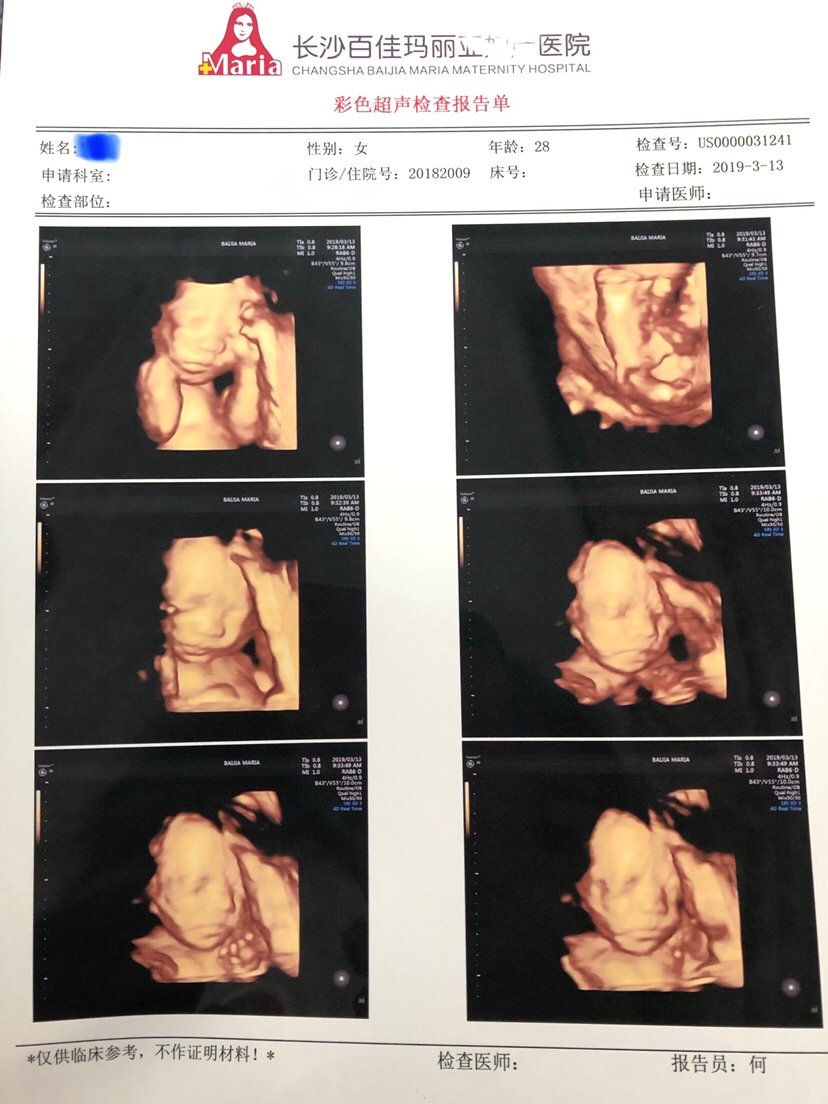

孕21周+2天

接四维顺利通过